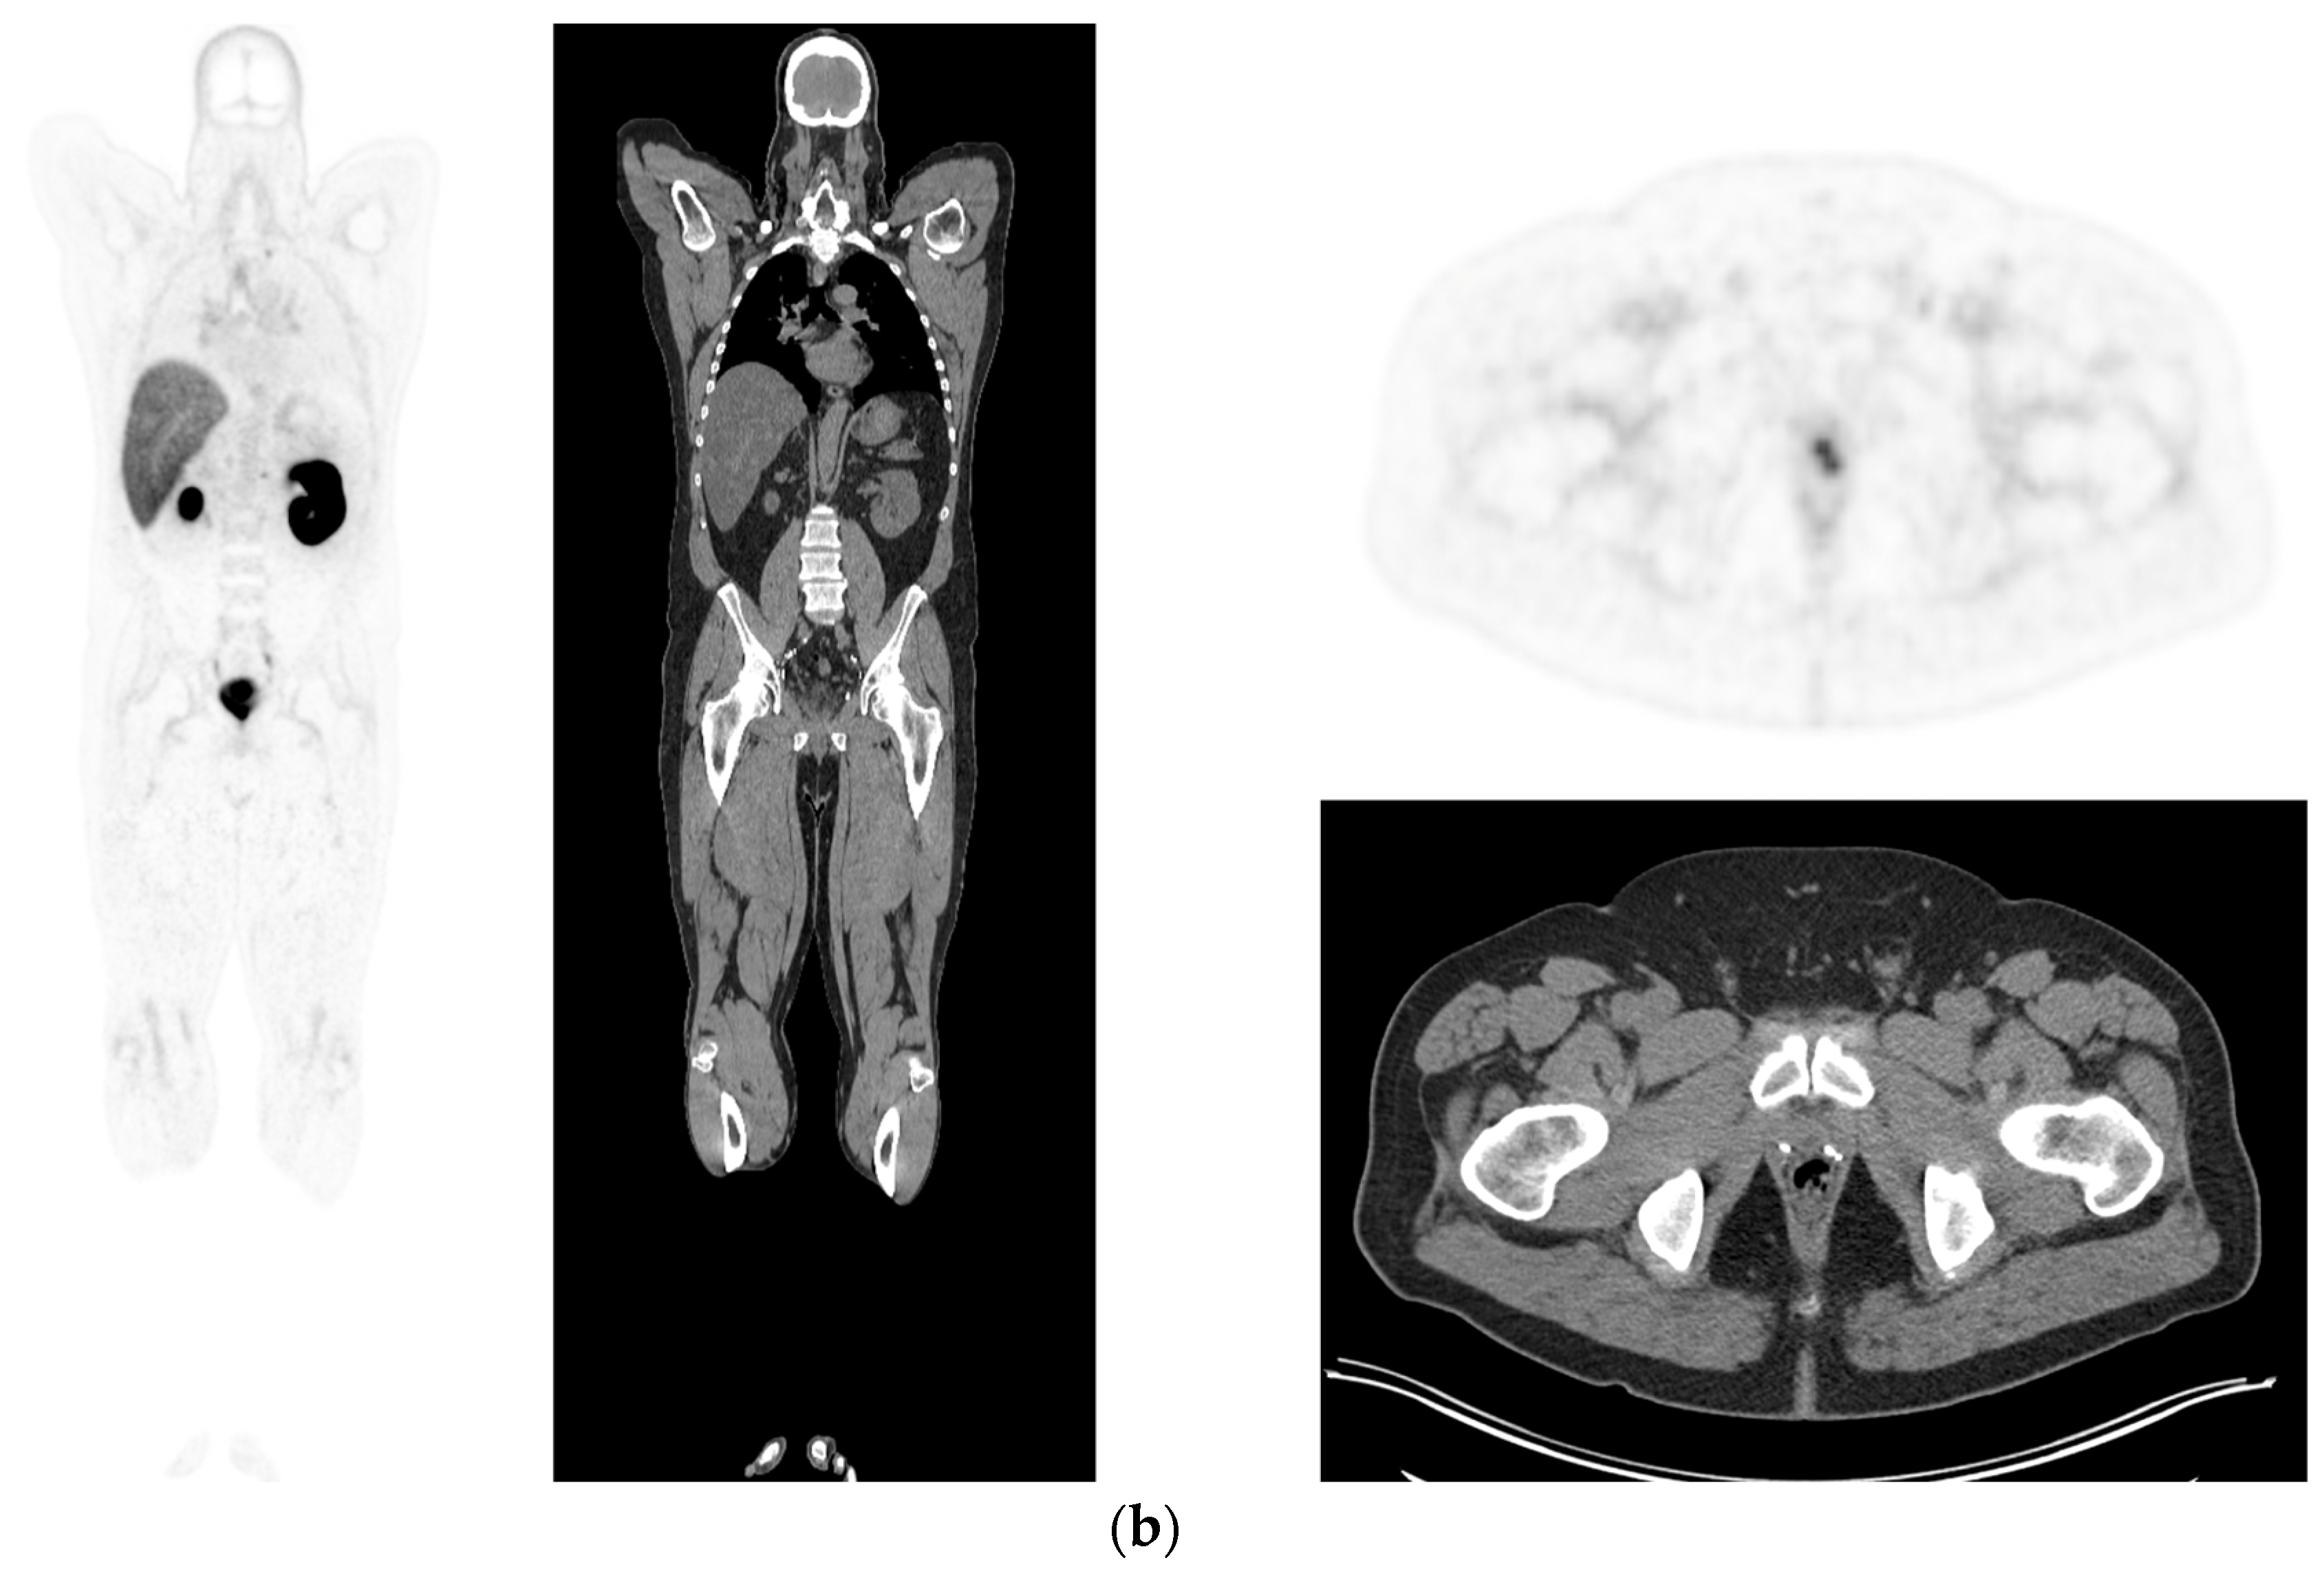

Figure 3.

Recurrent disease. 74 yr old M; radical prostatectomy 8 yrs prior; extensive para-aortic and upper pelvic lymph node involvement on CT; severe back pain; PSA 60. PSMA PET-CT: 68Ga-PSMA-216 MBq; uptake 48 min; BMI = 31.9; Wt 89 kg. (a,b): Coronal and sagittal images show bulky nodal disease with markedly increased uptake (SUV = 68.2) in abdomen and pelvis, hepatic metastases, multiple bony metastases in pelvis, lower limbs, sternum, ribs and vertebral column. (c): enlarged transaxial images of lower thorax/upper abdomen show tracer avid foci in segments 7 (SUV = 8.8), 4 (SUV = 8.7) of liver; X-hairs on lesion in right 10th rib, SUV = 14.6; CT on bone windows shows small region of sclerosis vs. extensive uptake on PET.